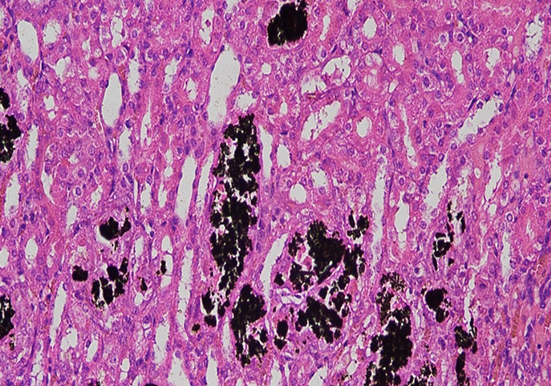

染色原理:利用银离子与组织中的磷酸钙盐或碳酸钙盐发生反应,在酸性条件下,钙盐中的钙离子被银离子取代,形成磷酸银或碳酸银沉淀。这些银盐沉淀在光照条件下,会发生光化学降解反应,被还原为黑色的金属银颗粒,从而使钙盐沉积部位在显微镜下呈现黑色或棕黑色,与周围未钙化的组织形成鲜明对比。